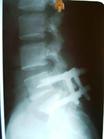

腰椎滑移的概念与治疗方案?

那是腰椎4,5节段吗?简单的说就是不稳定,